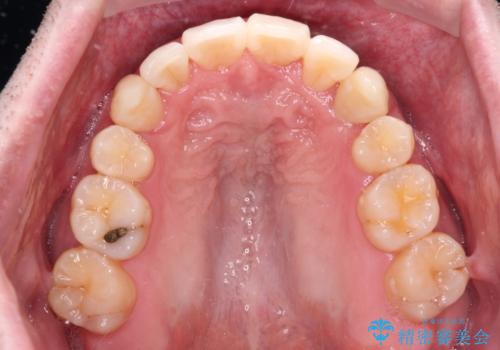

- 前歯のデコボコを気にして来院された患者様です。

叢生の解消とともに、前方に張り出した上顎前歯を引っ込めることを目的とし、上下左右の第一小臼歯4歯を抜歯をしてワイヤー矯正により治療することとしました。